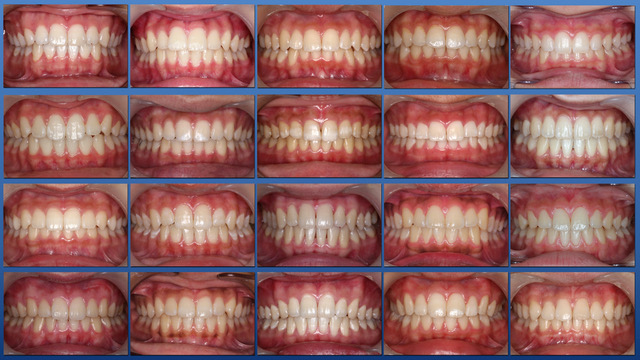

● 咬合育成

子どもたちを虫歯のないきれいな歯並びに誘導していくことが咬合育成で、歯並びが悪くなってから治療する矯正歯科治療とは異なる治療の仕方です。開業時から来院していたこどもたちをどうしたらきれいな歯並びにできるのかを研究してきました。いまではその成果が上がるようになり多くの子どもたちが健康できれいな歯並びをもつ大人になって来院するようになっています。この取り組みは歯科界でも評価され全国の歯科大学や歯科医師会からその分野の講演を依頼されるようになり書籍も出版されて当時はベストセラーになりました。いまでは咬合育成は全国の歯科医院で行われるようになっていますが須貝歯科医院の得意分野になっています。いつもポカンと口を開けて口で呼吸をしていたりするなど、きれいな歯並びになることを妨げる癖もありますがそれらを早く見つけて正しい機能を身に付けさせることも大切です。顎が小さくて歯が並びきらずにガチャガチャの歯並びになってしまうのが日本で一番多い歯列不正です。小さい頃から顎の成長を促す装置をつけて改善することを得意にしています。患者さんによっては矯正専門医に紹介しなければならないケースもあります。その時は地元の信頼できる矯正専門医をご紹介しています。

また乳歯から永久歯への生え替わりを注意してみていくことで多くの歯列不正は予防できます。できるだけ少ない介入できれいな歯並びになることを目指しておりその経験も豊富です。「定期健診に通っていたらいつの間にか虫歯のないきれいな歯並びになった」と思ってもらうことを目標にしています。